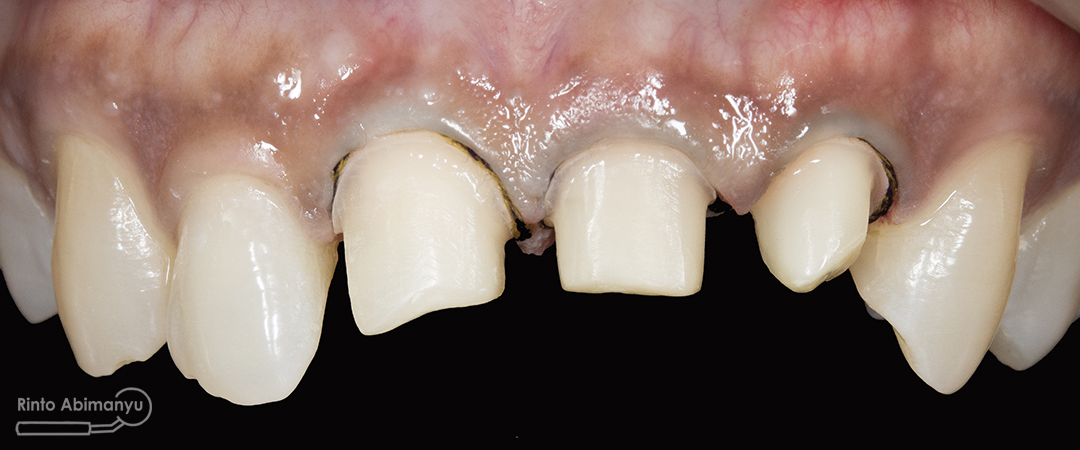

ini hasil preparasi gigi-giginya…

Hasil preparasi tampak depan

Hasil preparasi tampak oklusal